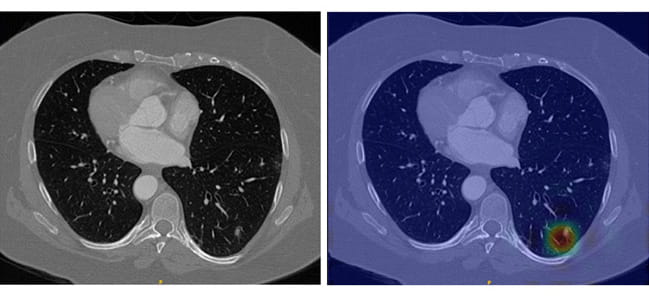

Lung nodules in an unaltered CT scan require sharp eyes for detection (left), but LungWeb highlights suspicious areas to make detection much less labor intensive (right).

The LungWeb system visualizes CT scan data on a pixel-by-pixel basis and can register differences at a high-resolution level that the human brain simply cannot match. The concept is that the software detects any nodules in the scan and clearly marks them so they are easy to identify. The radiologist can then quickly recheck the area to confirm the finding.

This is well supported by a study published in the journal Radiology that found a 49% mean sensitivity for lung nodule detection among radiologists reading chest CT scans, whereas LungWeb’s accuracy is projected to exceed 90%.

The downside to LungWeb at present is that it occasionally gives false-positive results by making mistakes that a human expert would not — for example, it may rarely detect a normal blood vessel and call it a nodule — so it will still be important for a radiologist to confirm the software’s findings. But Burt is continuously refining the software to eliminate these false positives, and he hopes to have LungWeb ready for a clinical trial by fall.